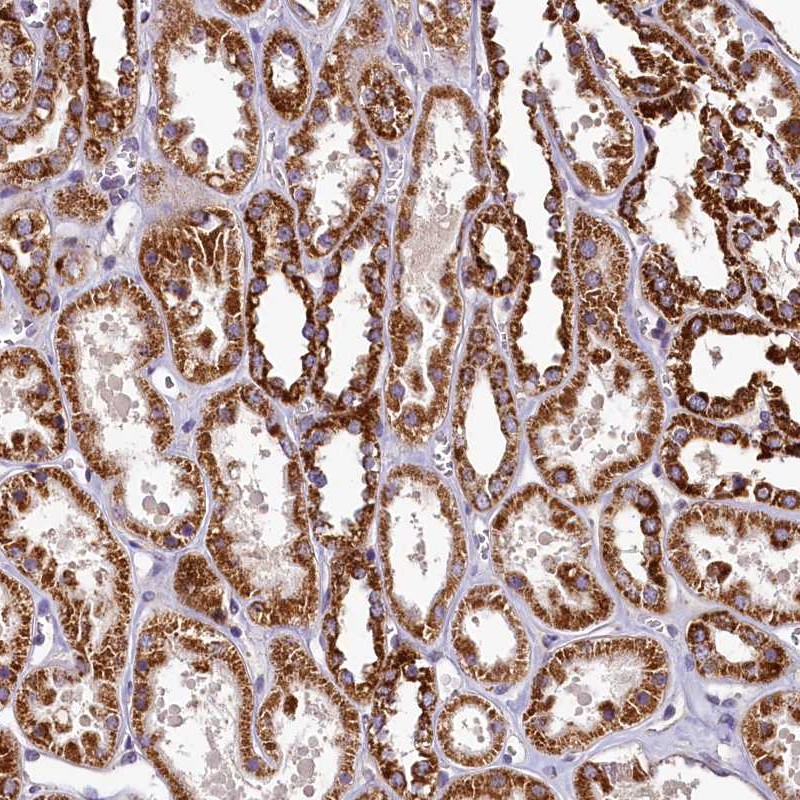

Immunohistochemical staining of human kidney shows strong cytoplasmic positivity in renal tubules.